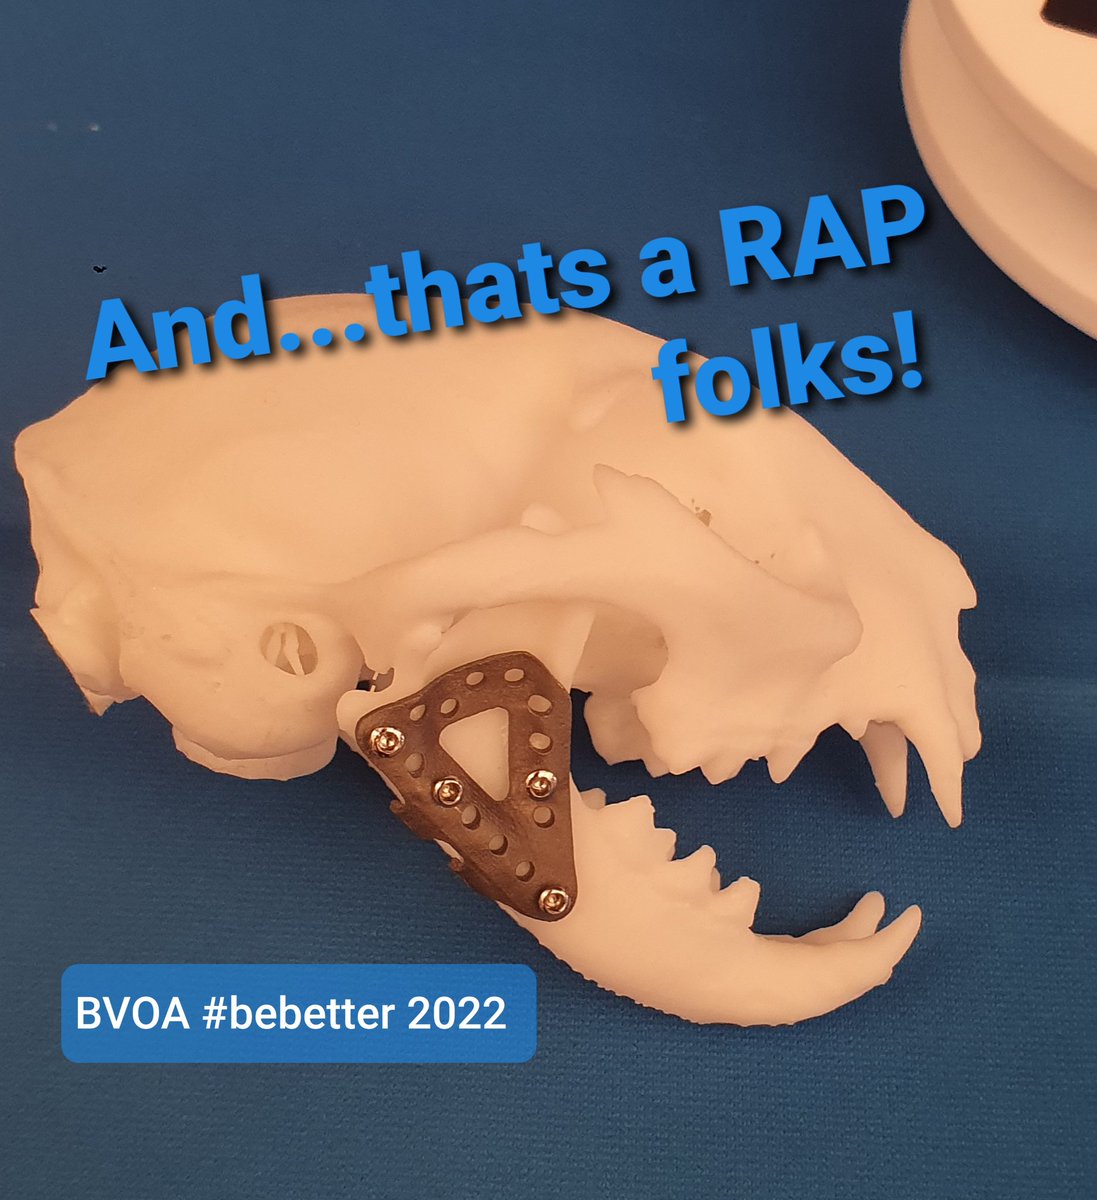

Our PhD student @FusionImplants Victor Lopez Tapia will be presenting @TheBVOA today, be sure to tune in.